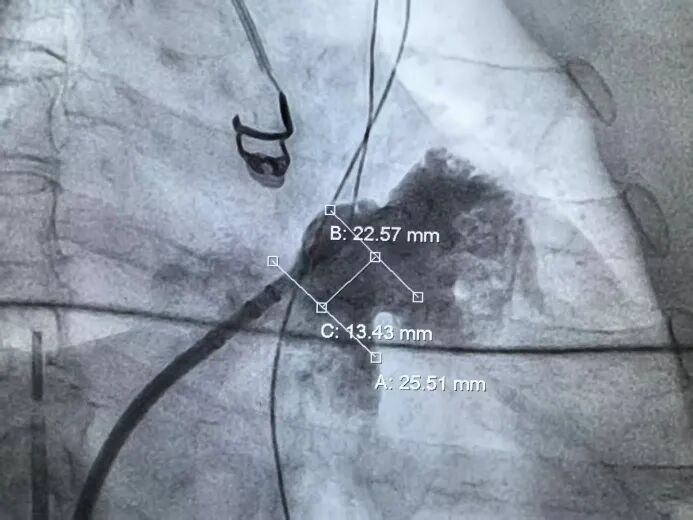

肝位左心耳测量锚定区:22.57mm,开口区:25.51mm。选择LAMax 2430型号封堵器。

肝位左心耳造影